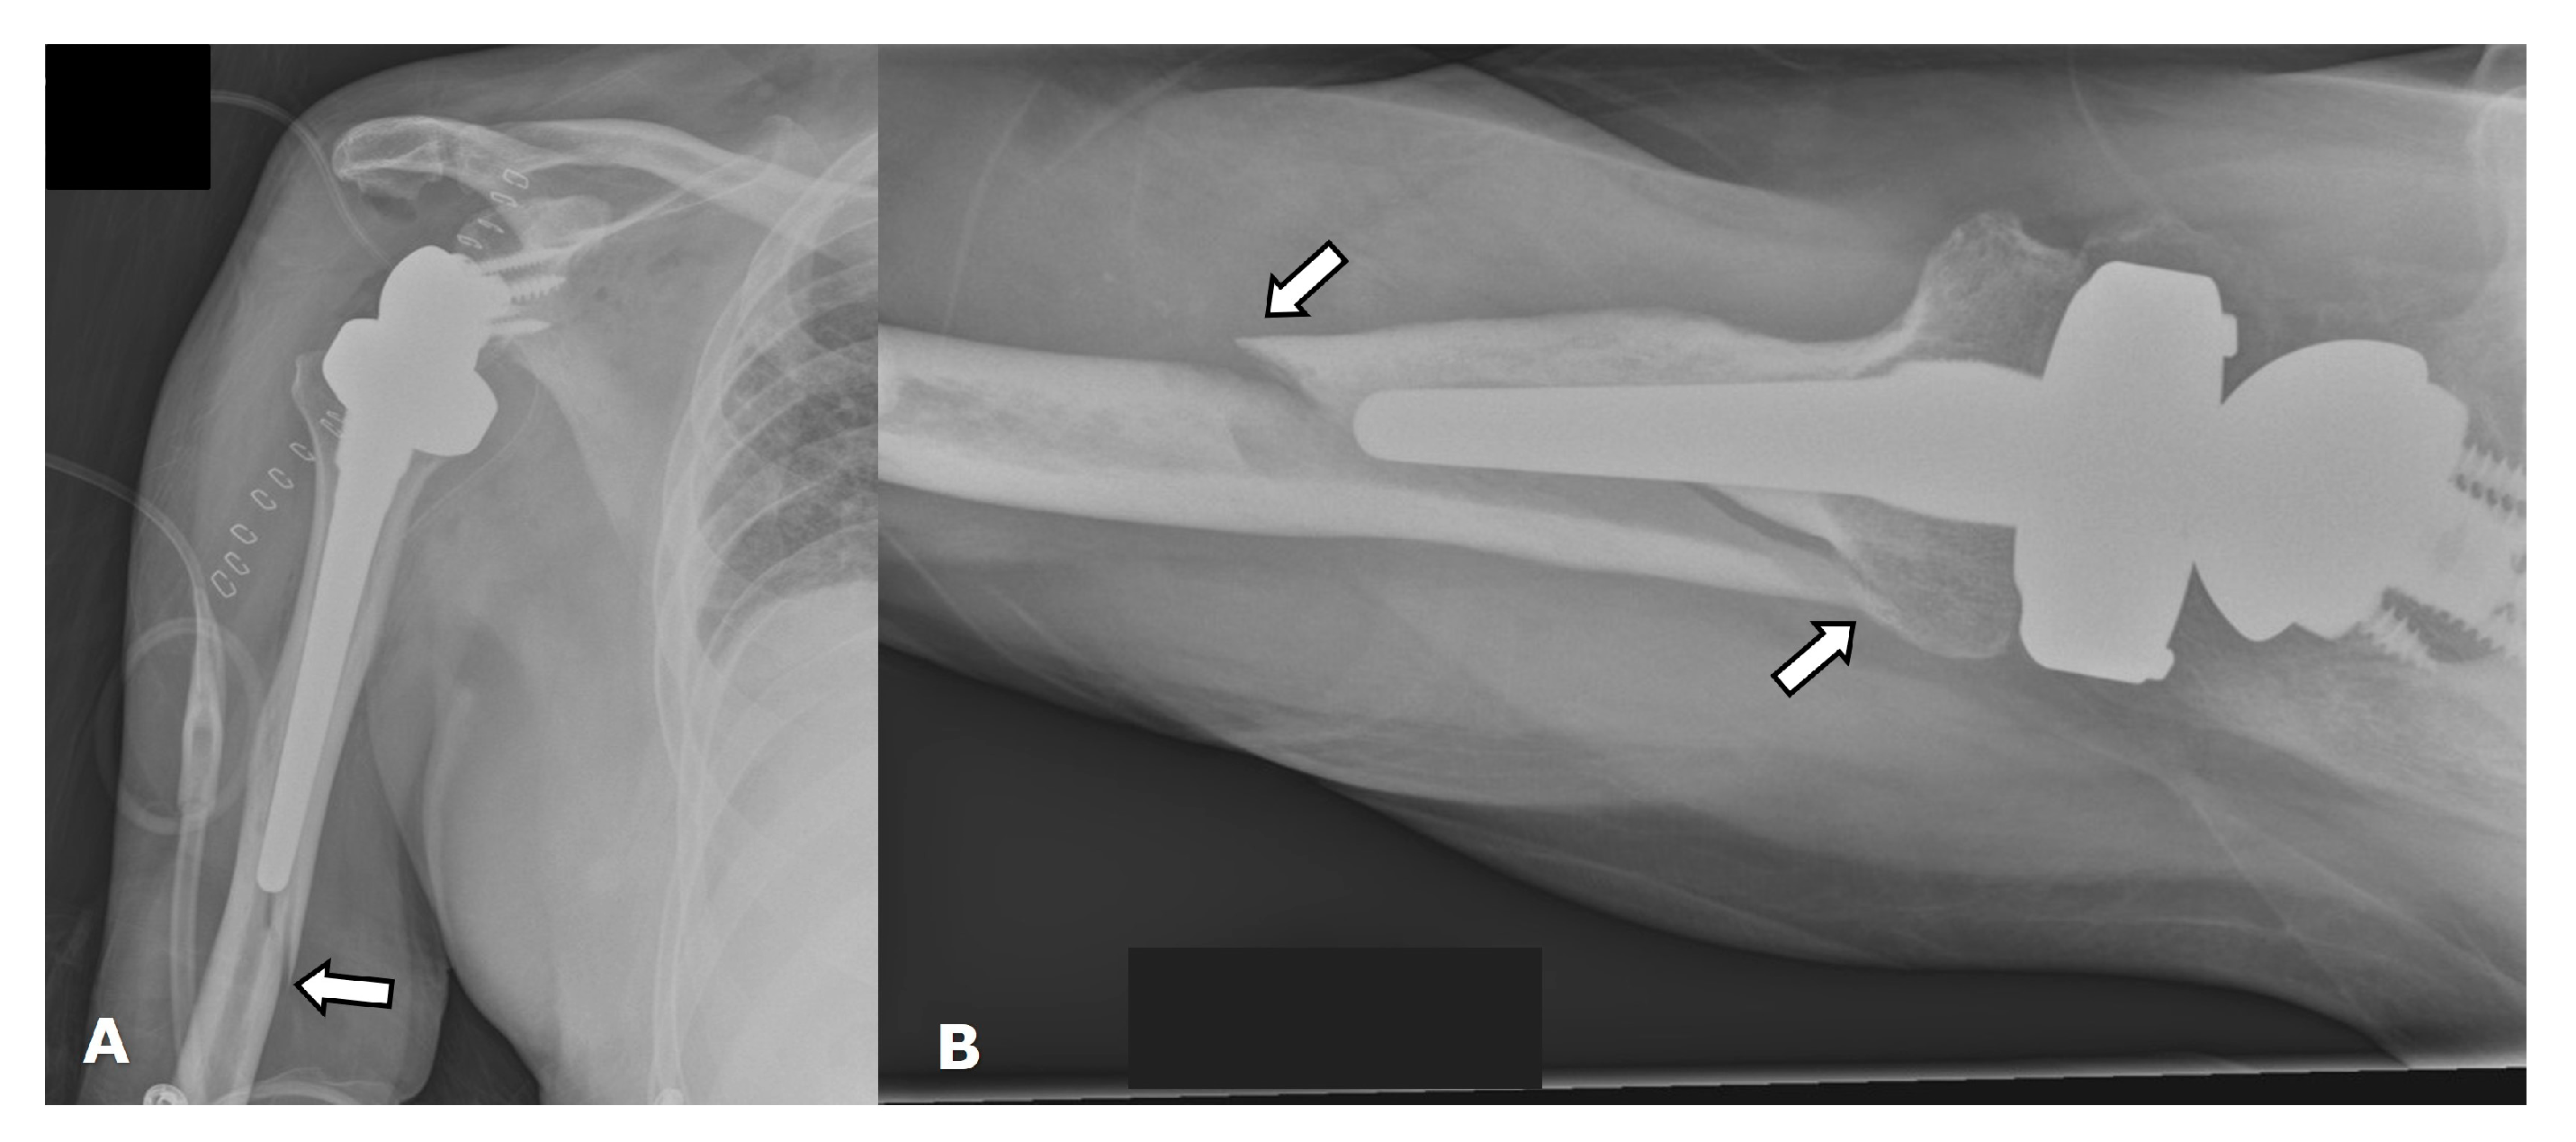

4.2.2. Stress Shielding and Fractures

4.2.3. Periprosthetic Joint Infection (PJI)